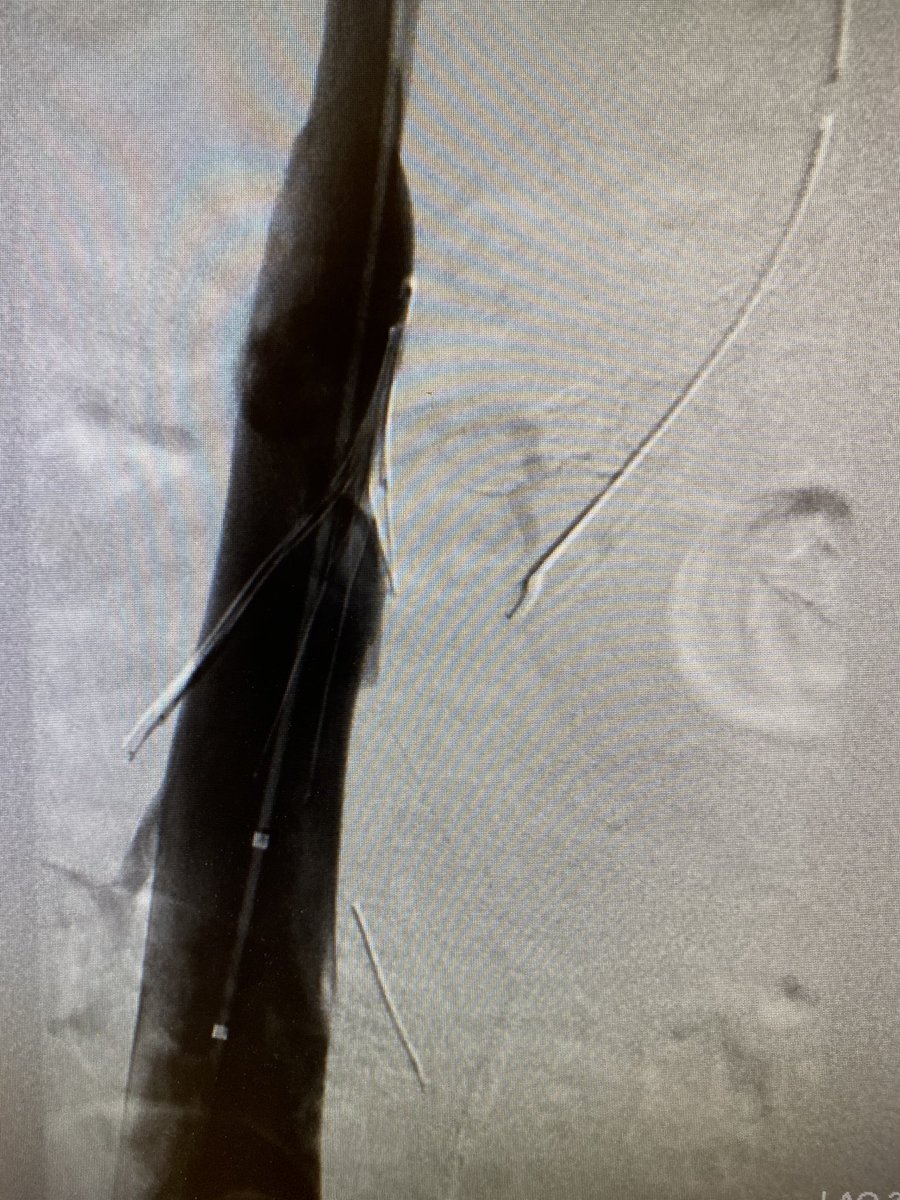

89 yo w/type 2 endoleak and growing aneurysm sac. Translumbar access followed by embolization with Onyx 34. #IRad #Onyx #endoleak @SIRRFS @SIRspecialists @GESTSymposium @SunilNarayanMD @ncdoro